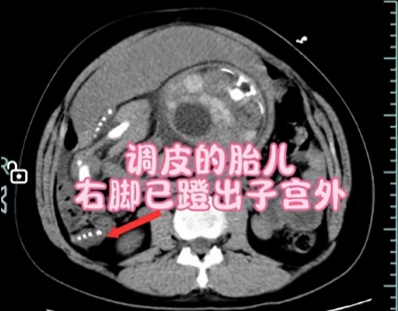

胎儿恰好一脚踢到了薄弱点,子宫破裂的同时胎膜早破后羊水全流进了腹腔,胎儿的腿死死地卡住了这个破裂口让孕妈妈没有出现即刻的大出血,掩盖了破裂的症状,这也就解释了为什么小豆的羊水突然“人间蒸发”了,并且又腹痛不止,其实是她的身体在呼救。从锁定“子宫破裂”致命元凶,到新生儿响亮啼哭,医生用时18分钟托住了两条命。

还有网友调侃说:“魔童降世,好家伙”“调皮的娃遇到了好的医生”“惊心动魄,好在有惊无险”。